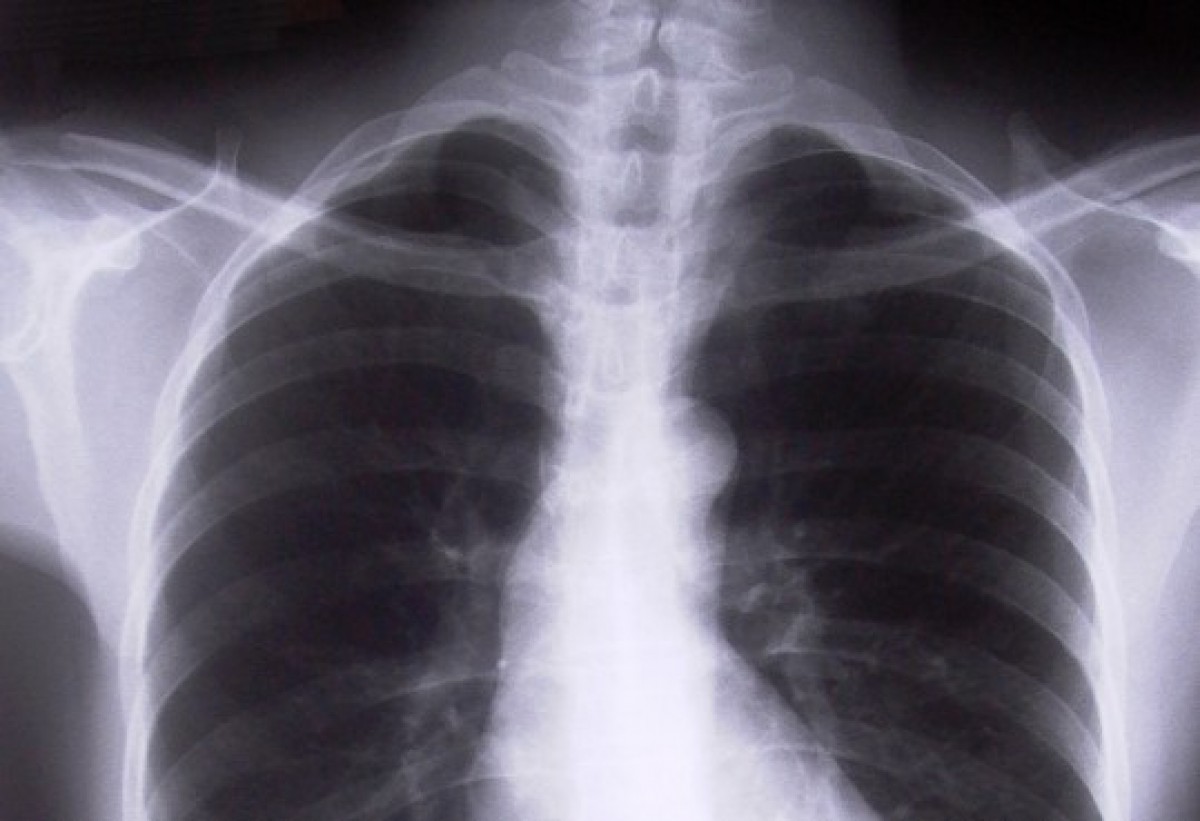

Arī Latvijā, līdzīgi kā citās pasaules valstīs, pieaug saslimstība ar zāļu rezistento tuberkulozi.

Šā gada astoņos mēnešos Latvijā reģistrēti 567 pirmreizējas tuberkulozes gadījumi, tajā skaitā 84 multirezistentas tuberkulozes jeb gadījumi, kad tuberkulozes izsaucējs ir nejutīgs pret kādām no prettuberkulozes zālēm, liecina Tuberkulozes un plaušu slimību centra dati.